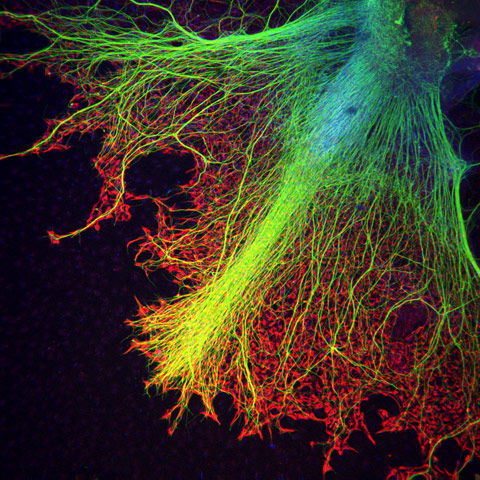

También hay imágenes provenientes de España, como la del prestigioso investigador Juan Carlos Izpisúa del Centro de Medicina Regenerativa de Barcelona, en la que se pueden ver neuronas creciendo sobre astrocitos.

Juan Carlos Izpisúa, Neuronas creciendo sobre Astrocitos (20X). Nikon Small World 2011.